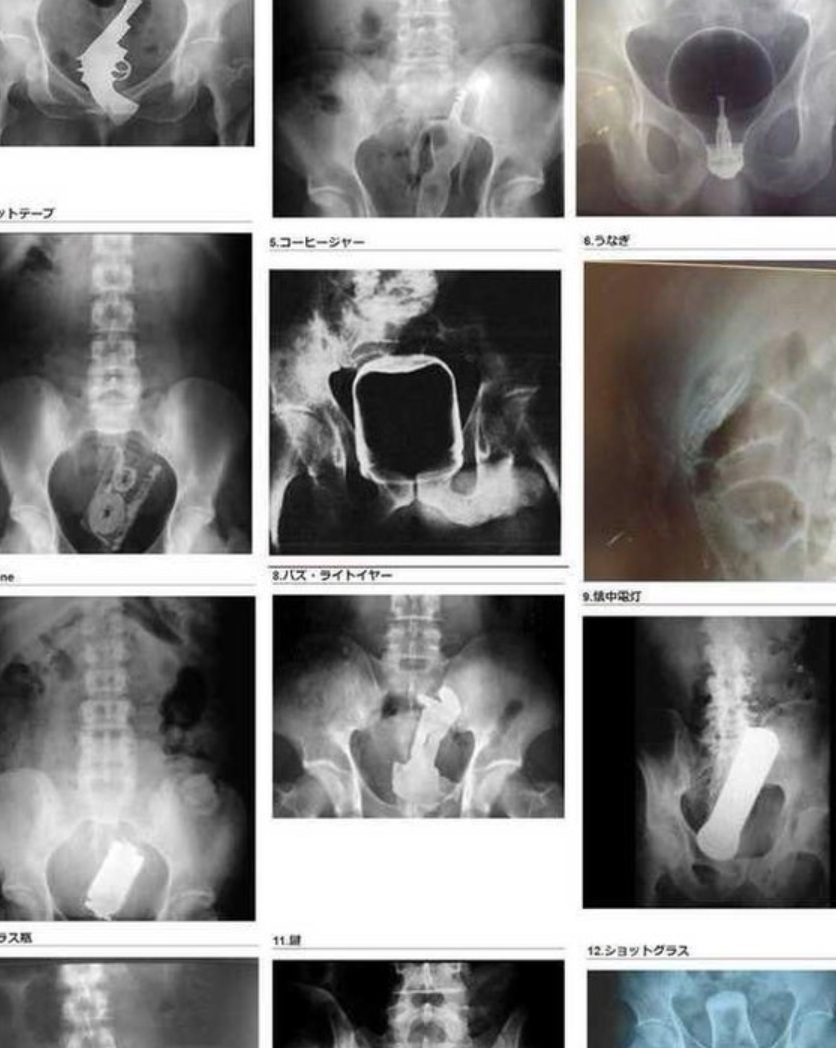

その結果こういう悲劇が起こる・・・

【闇】”直腸に異物”、全く笑えない

カセットテープ突っ込んだ奴はラリってたのかね

みたいに笑ってたけどその上のバズ・ライトイヤーで完全に腹筋持ってかれたわ。一体何を思い立ってそんなブツ入れようと思ったんだよ。